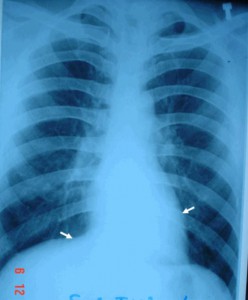

Những điều cần biết về chụp X-Quang viêm phế quản ở trẻ em

Viêm nhiễm đường hô hấp là bệnh phổ biến ở trẻ em. Những dấu hiệu trên lâm sàng của những bệnh này tương đối giống nhau. Nên xét nghiệm là điều ...